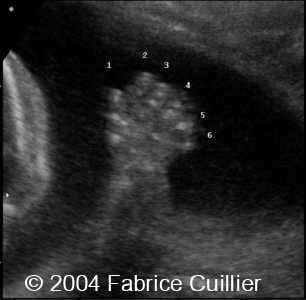

What is Polydactyly?

extra fingers or toes.

Polydactyly

Polydactyly